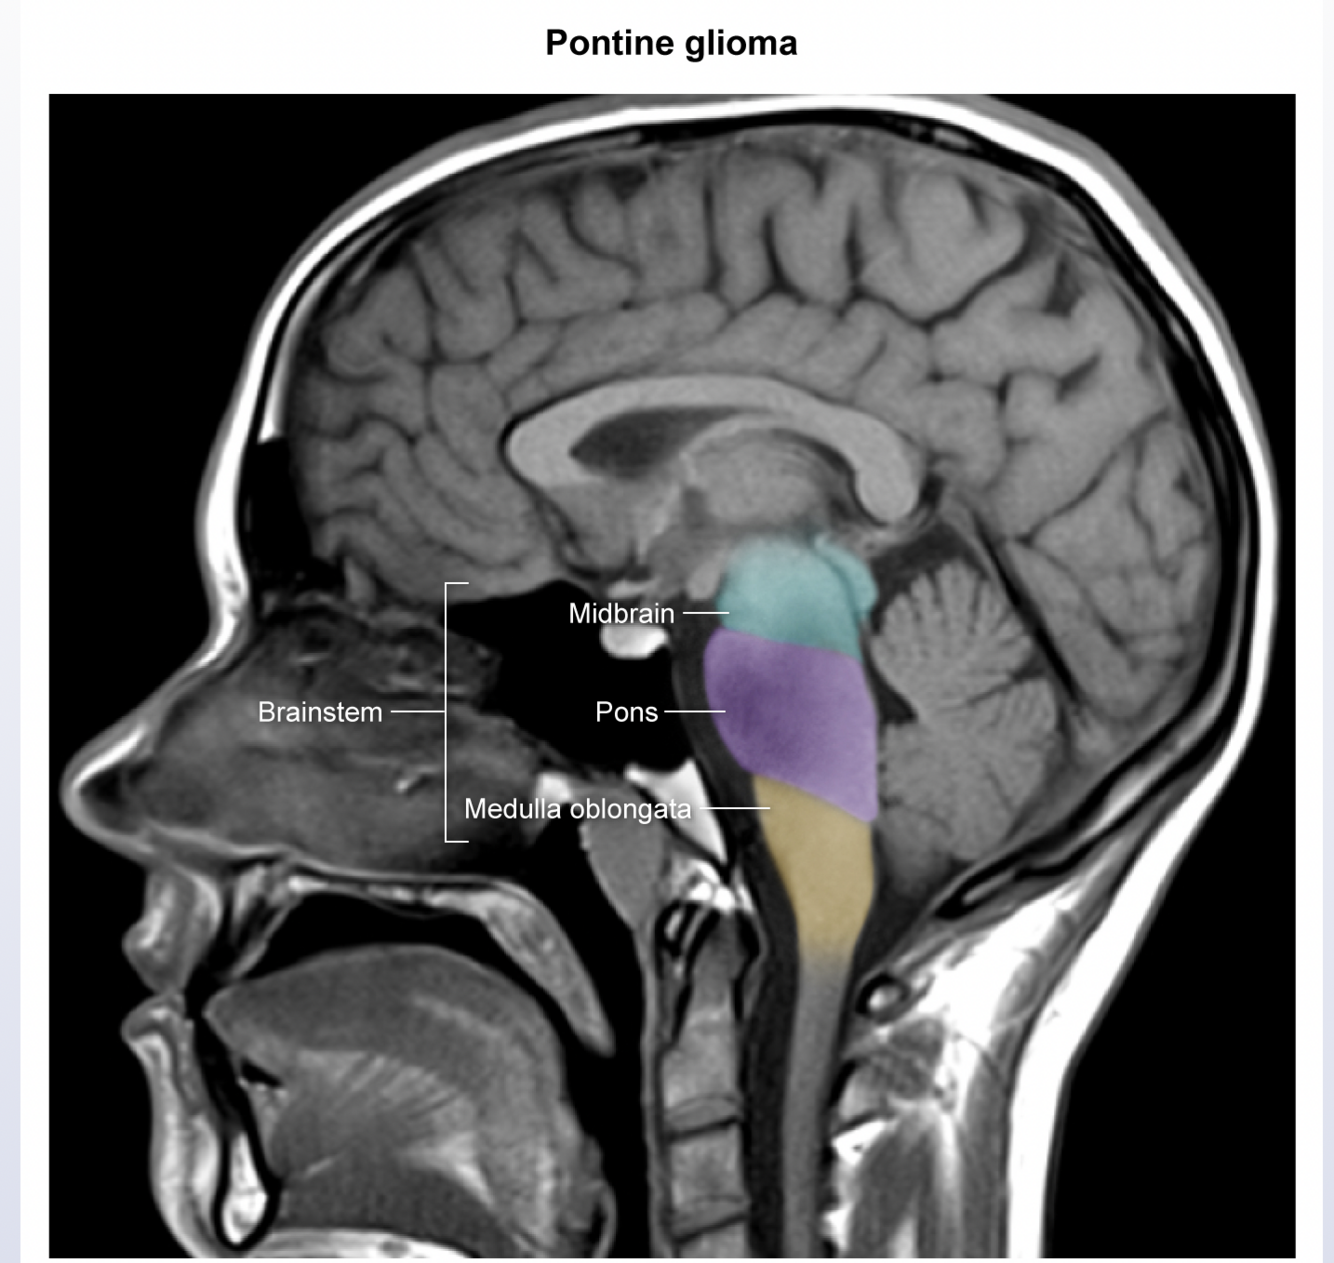

Pontine glioma

the nuclei of the vestibulococchlear nerve (CN VIII) are located in the pons; CN VIII conveys information about head position and movement and helps to stabilize the gaze during head movement; damage can lead to nystagmus